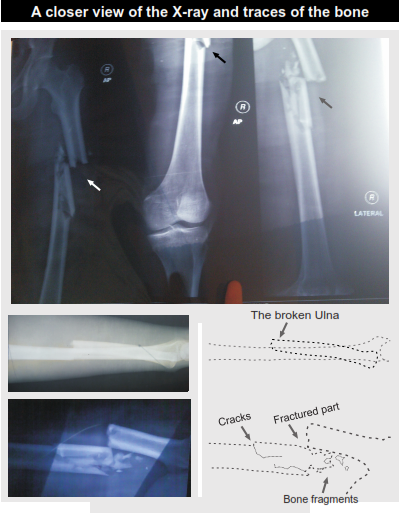

img20.png PICTORIAL REPRESENTATIONS img21.png